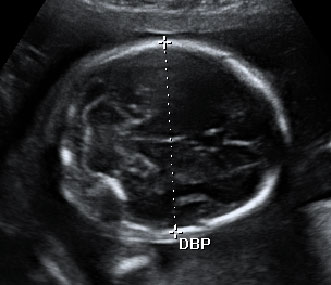

En la 20 semana de gestación, los órganos sexuales del feto, masculinos o femeninos, ya están formados y son visibles, especialmente con una ecografía en 4D. Aquí la imagen ha captado el sexo de un niño.

Ecografía semana 20: sexo masculino

En la imagen podemos ver un feto de 20 semanas y 6 días de gestación del sexo masculino.